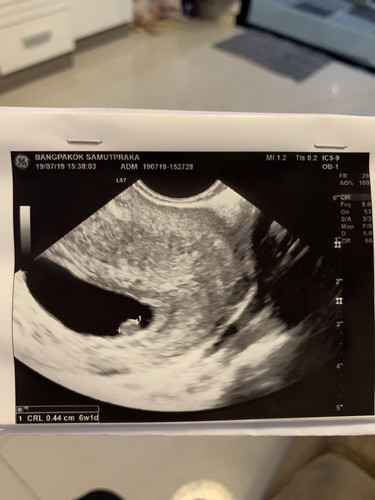

ในรูป6wนะค่ะของเราอัตร้าซาวด์6wก็ตัวเเค่นี้เหมือนกันค่ะเเต่มีเสียงหัวใจเต้นเเล้ว

ในใบซาวด์คุณแม่พึ่งขึ้น 6 week 1 day เองนะคะ ลองถามคุณหมอดูค่ะ